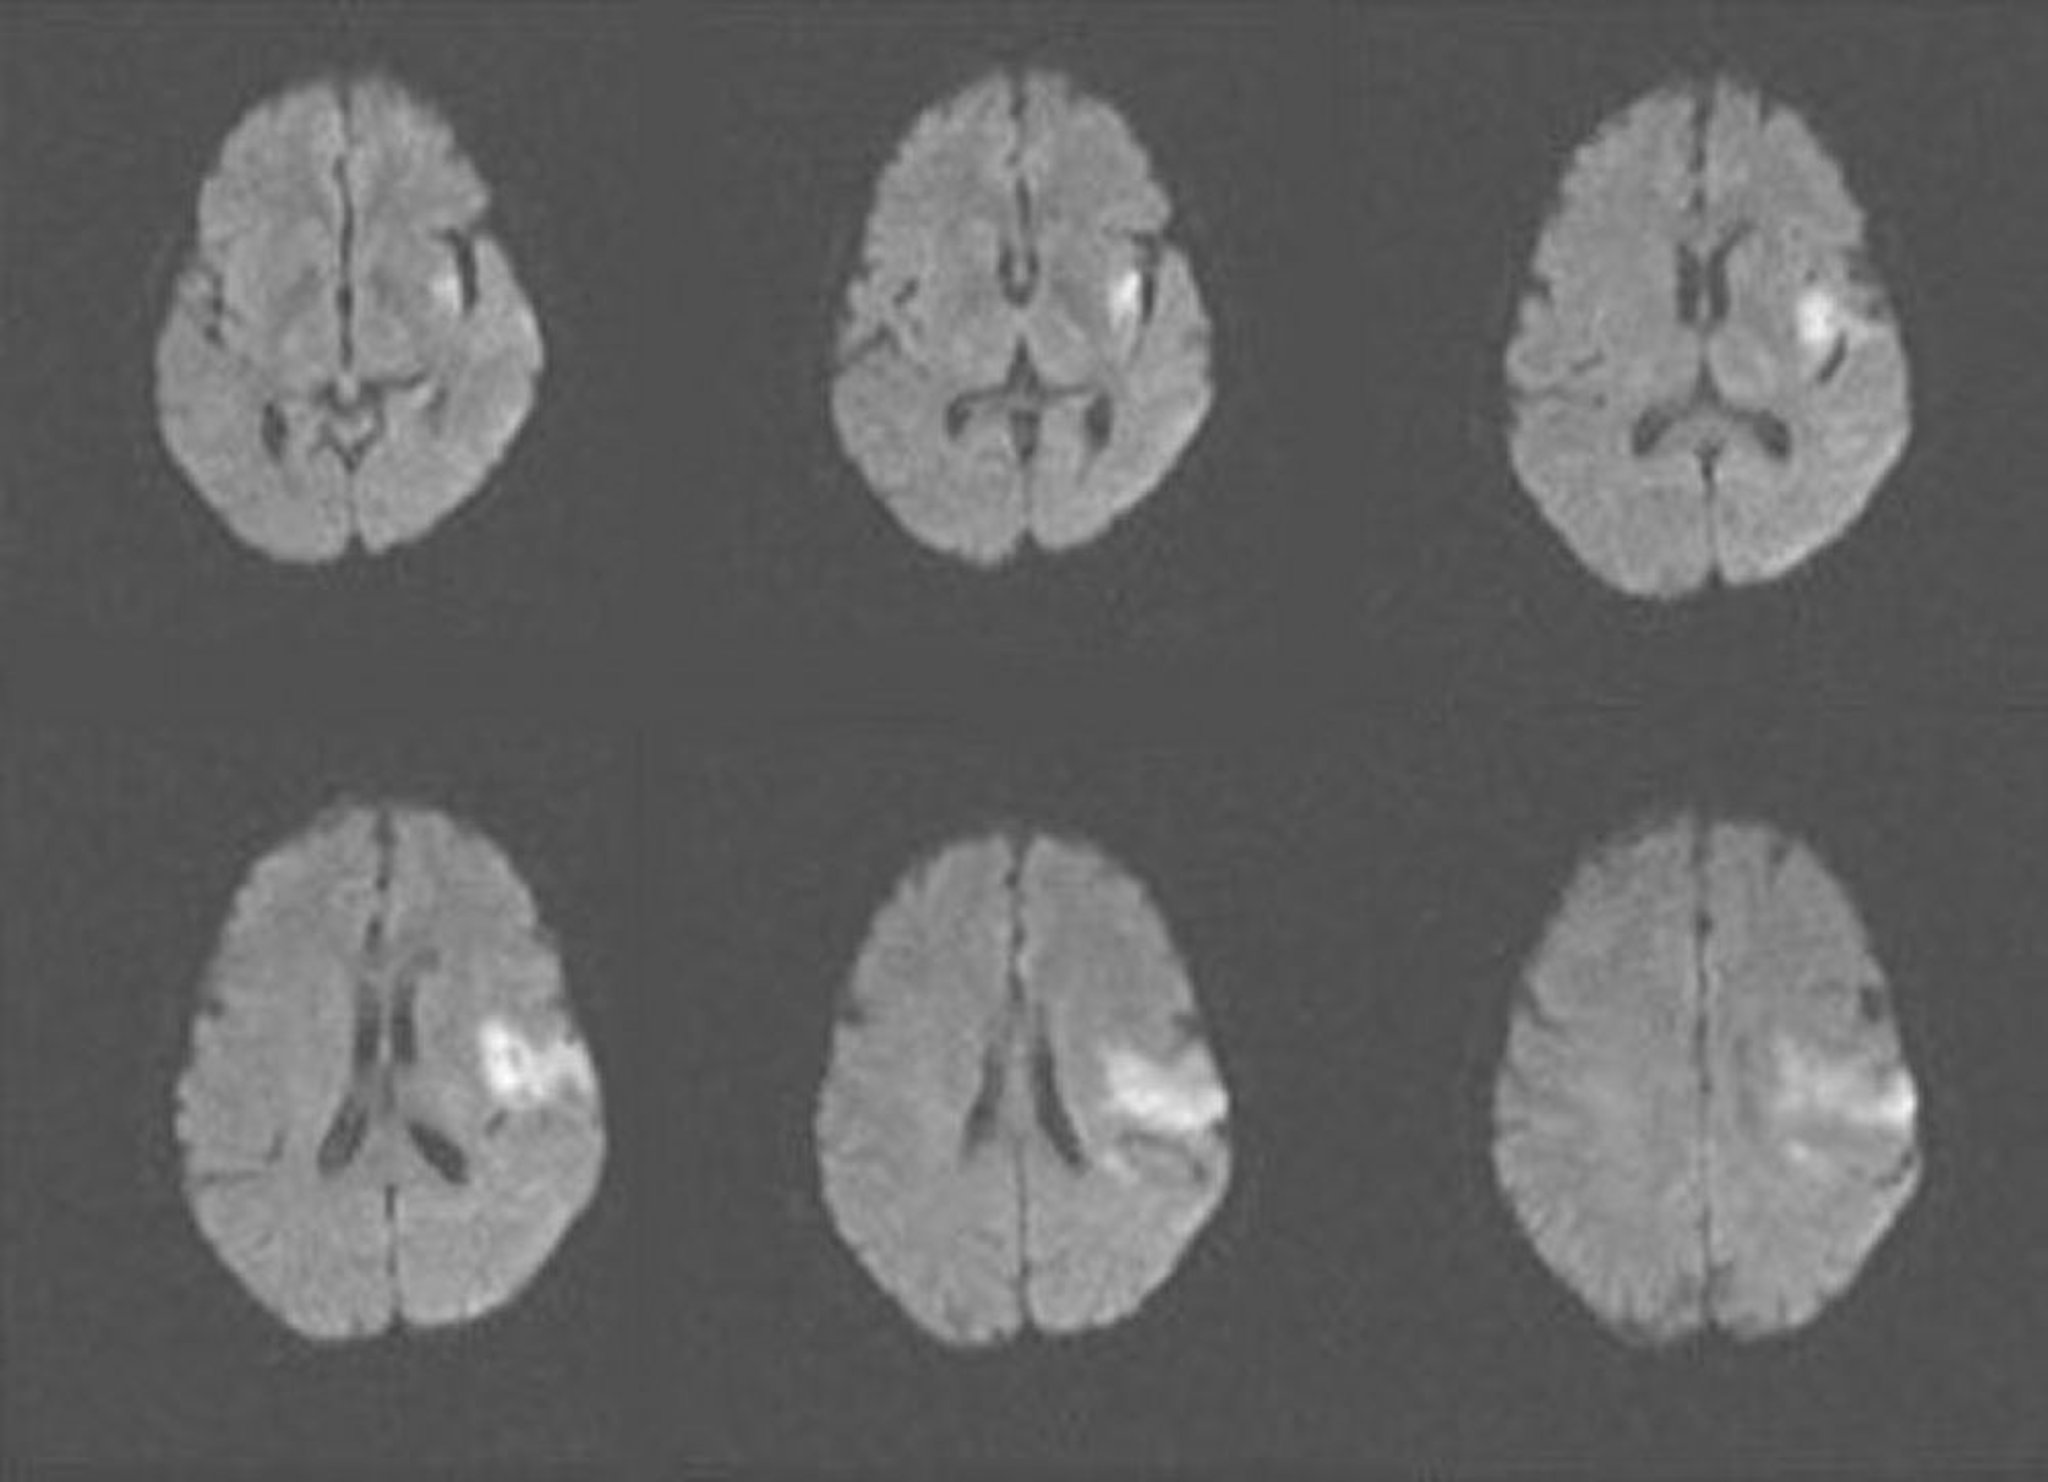

Accidente cerebrovascular isquémico agudo (RM)

Esta RM muestra un área de difusión restringida compatible con un accidente cerebrovascular isquémico agudo en los lóbulos insular y frontal izquierdo.

Image courtesy of Ji Y. Chong, MD.